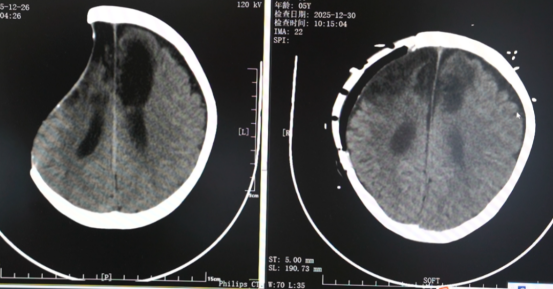

然而,术后凌晨,创伤 ICU 主管医生何郭一石发现孩子一侧瞳孔散大,CT提示脑疝,颅内损伤加重。凌晨4:37,患儿再次被推进手术室进行开颅手术。马涛与神经外科薛祎腾、刘洋医生并肩作战,清除右侧颅内血肿并进行去骨瓣减压。从开胸到开颅,医护人员在手术室与创伤ICU之间来回奔波,为孩子跑出了一条生命通道。